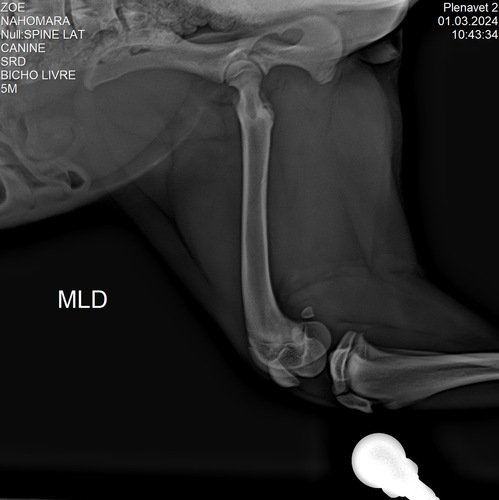

Nossa família adotou ela fazem 3 meses e ela está com a patela machucada ! Sendo assim precisa de uma cirurgia !!! 3.700,00 valor inicial sem os remédios! Já gastamos mais de mil reais até agora em remédios e consultas exames!!!